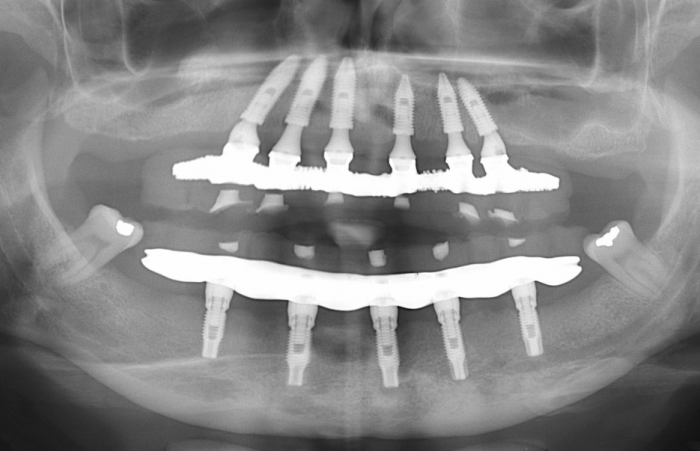

Raio X final

Próteses fixas superior e inferior, sobre implantesdo caso finalizado em janeiro de 2011